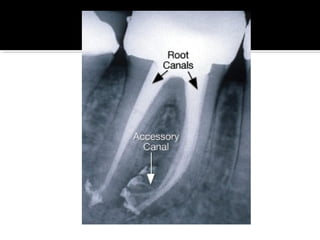

 Accessory canals are branches of the main

canal that form a communication between the

pulp and periodontum.

 They also contain vessels and nerves, and can

be located anywhere between the level of

furcation to the apex.